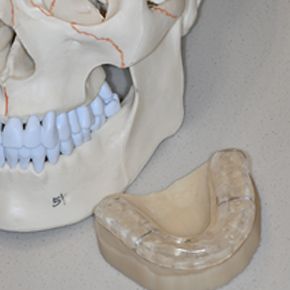

스플린트

환자 맞춤으로 제작된 장치를 치아에 장착하여, 턱관절과 주변 근육의 과도한 긴장을 줄이고, 턱을 안정화시켜 줍니다.